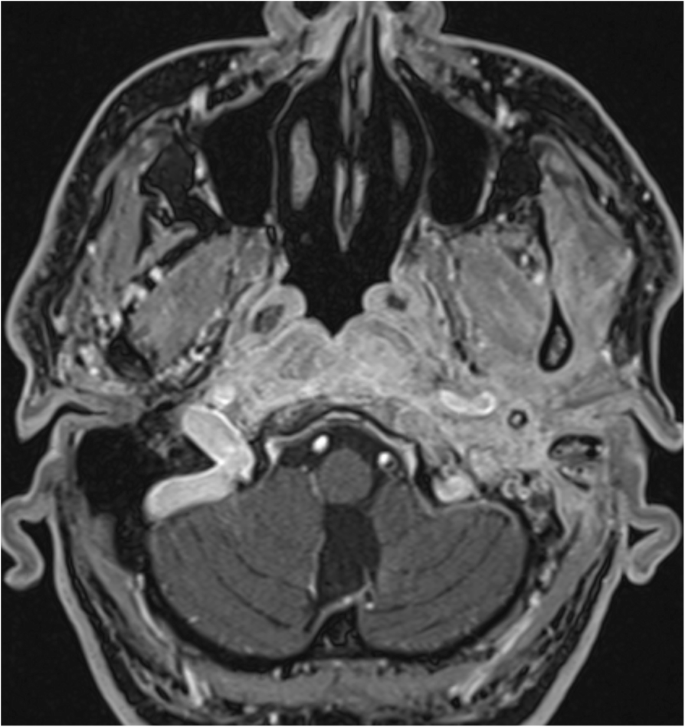

Day 93–177. Gadolinium-enhanced MRI, axial plane, T1-weighted, with fat suppression. The signal increases homogeneously on the left side in retrostyloid and pre-styloid regions, longus colli muscle, and Eustachian tubes on both sides. The signal mildly and homogeneously increases in the temporomandibular joint, lateral pterygoid, and masseter muscles on the left side. Bone marrow shows signs of infiltration in the basal part of the occipital bone

Additionally, MRI investigations in the early stage of the disease again illustrated fluid in the mastoid cells and oedema of the soft tissues adjacent to the external ear canal. Soft tissue enhancement was visible on axial gadolinium-enhanced T1-weighted imaging, originating from the digastric muscle insertion and continuing to the insertions of the musculus longus capitis and musculus rectus capitis anterior (Fig. 8). The pharyngobasilar fascia was in close contact with the pharyngeal process of the ossis occipitalis in the middle line, and represented the frontal border of the infection. Contralateral spread beneath the clivus in the retropharyngeal space was consistently noted. In advanced stages of infection the butterfly-shaped soft tissue enhancement was located underneath both petrosal bones and the clivus (Figs. 6 and 7). Progression of infection from the temporal bone to the other skull base bones was not noticed, except for progression through the fissura sphenooccipitalis towards the occipital bone (Fig. 8). When the treatment proved to be successful, gradual improvement of inflammatory changes in the individual regions was observed (Figs. 9 and 10).